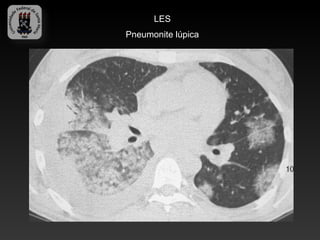

-LUPUS ERITEMATOSO SISTÊMICO

-Mais comumente afeta mulheres jovens

-Doença pleuro pulmonar ocorre em mais da metade dos pacientes

-Pleurite, pneumonite inflamatória(lúpica), fibrose pulmonar interticial,

hipertensão pulmonar, pericardite, disfunção diafragmática, hemorragia

alveolar difusa.

-Pneumonite lúpica é pontencialmente fatal (opacidades intersticiais, vidro

fosco, febre e hipoxemia)

-Hemorragia alveolar (opacidades em vidro fosco com espessamento

septal)

LES

Pneumonite lúpica

Hemorragia alveolar